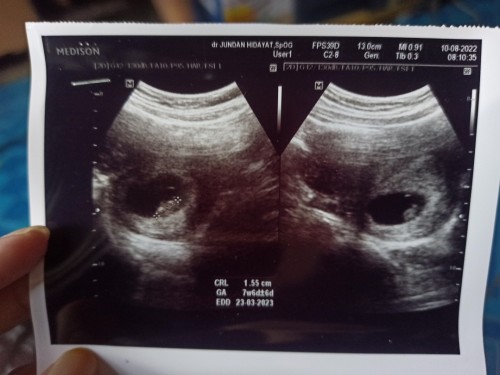

Sy USG kmrn bun, uk 7w6d udh ada janinnya + djj ny udh jls